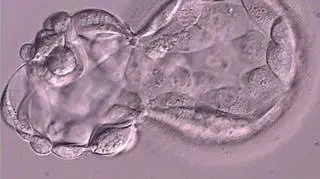

Wylęgająca się blastocysta - V doba hodowli

Jeśli embrion jest w stadium blastocysty, może zagnieździć się od razu w macicy, jeśli jest podany wcześniej - musi w organizmie kobiety dojrzeć.

Blastocysta to ostatni etap rozwoju zarodka, który można osiągnąć w warunkach laboratoryjnych. Hodowla zarodka do stadium blastocysty może zwiększać szanse na pozytywny wynik metody in vitro.